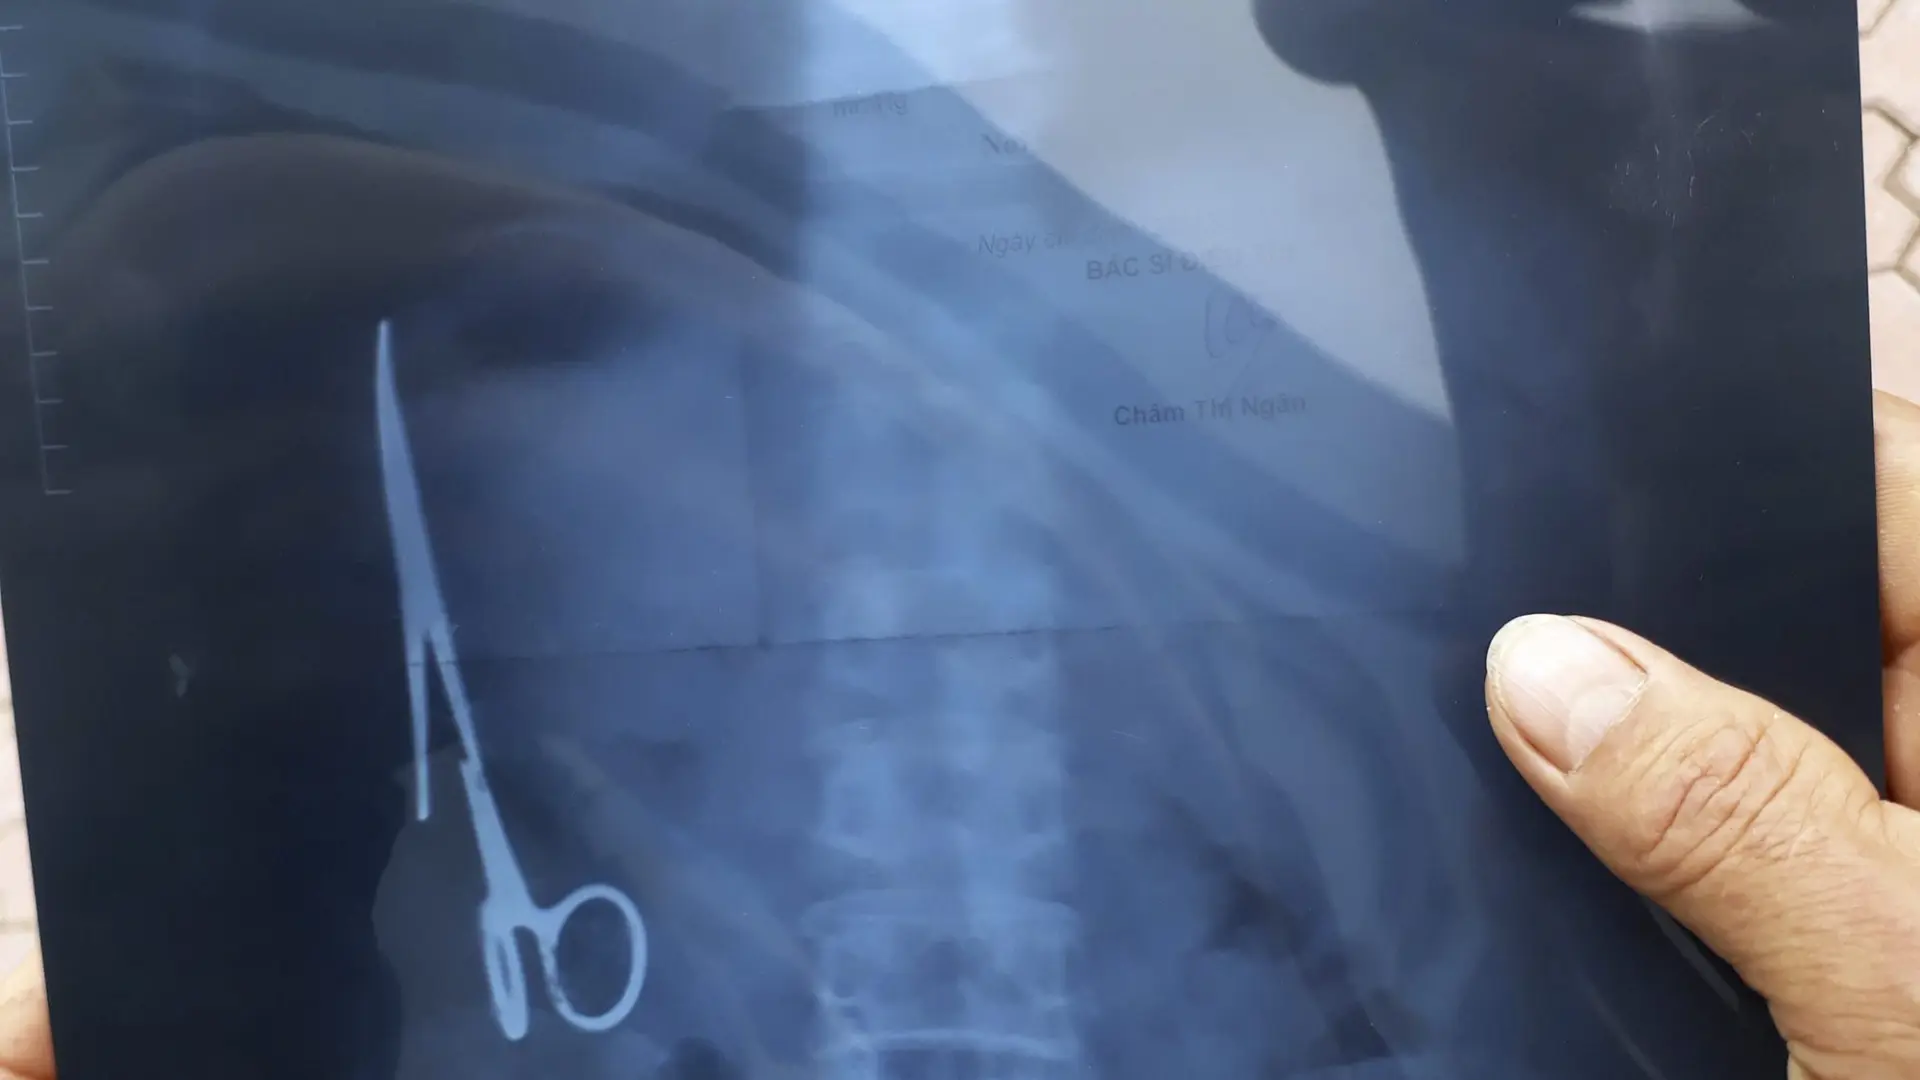

проглотил стекло

Что будет если случайно проглотил стекло 107 фотографий